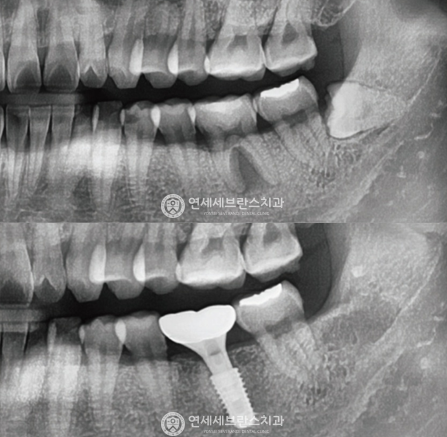

윗 턱뼈가 얇아 임플란트 식립이 어렵다면?상악동거상술

상악동 거상술은 치조골 높이 부족으로 임플란트 시술이 어려운 경우,

상악동을 이용하여 인공 뼈를 이식함으로써

임플란트 시술을 가능하게 하는 중요한 수술 기법입니다.

02

잇몸뼈의 양이 부족해 임플란트 식립이 어렵다면?뼈이식 임플란트

성공적인 임플란트 식립을 위해서는 충분한 양과 질의 잇몸뼈가 필수적이지만,

경우에 따라 잇몸뼈가 부족한 경우가 있습니다.

이 경우 뼈이식술을 통해 먼저 잇몸뼈의 양과 질을 개선한 후

임플란트를 식립해야 장기적인 안정성과 성공률을 높일 수 있습니다.